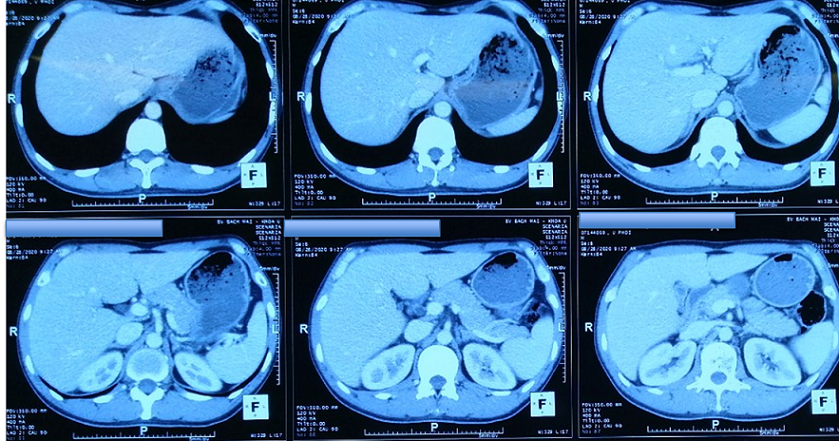

Chụp cắt lớp vi tính ổ bụng:

Hình 2: Hình ảnh chụp cắt lớp vi tính ổ bụng chưa phát hiện tổn thương thứ phát.